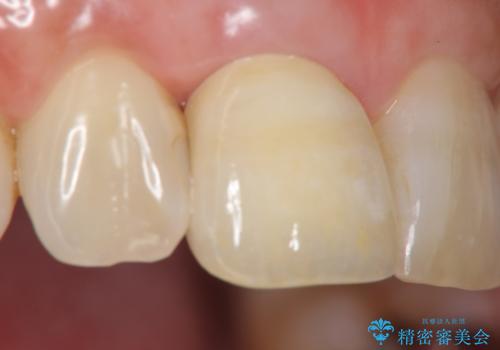

金属のフレームを用いるクラウンは色調が暗くなる傾向にありますが、セラミッククラウンに置き換えたことで自然な明るさ、審美性を取り戻すことができました。